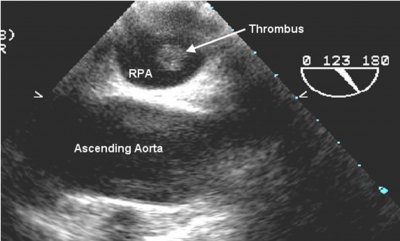

There is a rare potential to directly visualize large pulmonary emboli with TEE (Figures 7a and b).

Figure 11

Figure 12

However, the manifestations of right heart strain can be much more easily appreciated. Such findings may include right ventricular (RV) dilatation and/or hypokinesis, tricuspid regurgitation, pulmonary hypertension, and pulmonary artery or inferior vena cava dilation. 9 McConnell’s sign, which describes preservation of the RV apex but akinesis of the mid-RV free wall has a 77% sensitivity and 94% specificity for pulmonary embolism (PE). 10